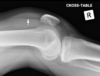

Intracapsular NOF

Colles’ fracture